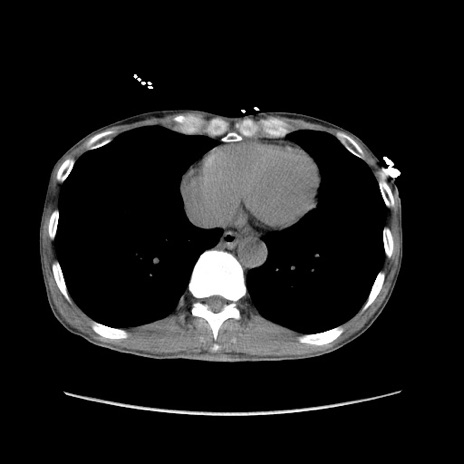

症例11(横断像)

【症例】 60歳代男性

【主訴】 下腹部痛

【現病歴】 本日夜中より下腹部痛の症状認め、受診。

【既往歴】 膀胱癌(膀胱全摘+尿管皮膚瘻術) 、胃癌術後

【身体所見】 BT 35.3℃、PR 58/min、BP 136/98mHg、腹部平坦、軟、腸蠕動音±、ストマ留置あり、左上腹部~正中部に圧痛あり、反跳痛なし。

【データ】WBC 5100、CRP0.01